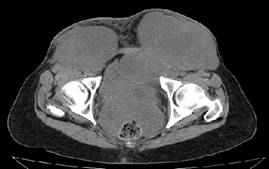

Figura 1: Tomografía computarizada simple de pelvis, cortes a 3 mm con reconstrucción MPR sagital